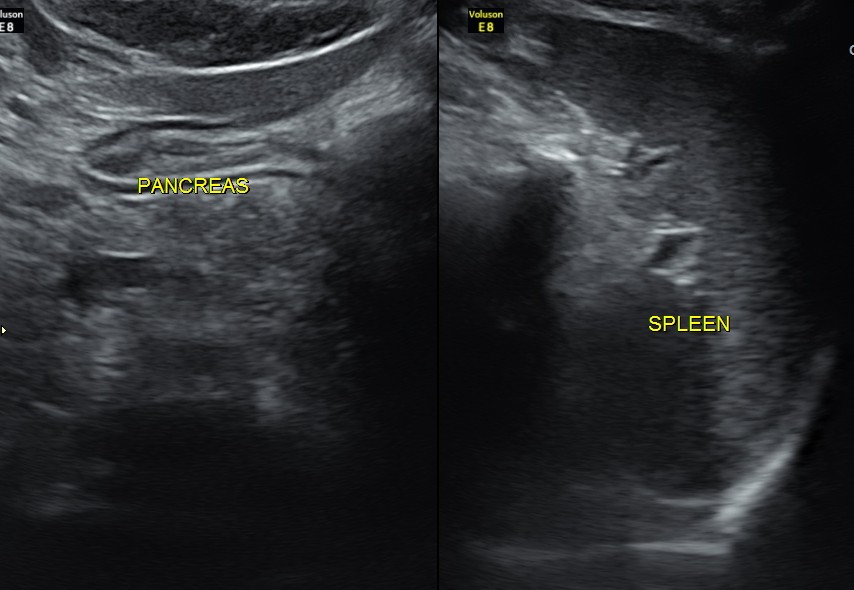

Liver, gall bladder , pancreas, spleen and the left kidney were normal . The prostate showed mild enlargement.